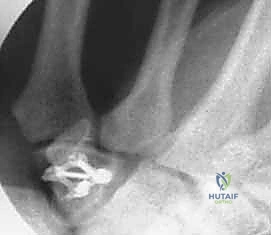

| التقنية المستخدمة | جبس فايبر جلاس مخصص. | مسامير دقيقة (Headless screws)، أسلاك كيرشنر، منظار 4K. |

4. التثبيت الداخلي (Internal Fixation)

يتم تثبيت العظام باستخدام أدوات طبية متناهية الصغر مصنوعة من التيتانيوم.

* أسلاك كيرشنر (K-wires): تُستخدم للتثبيت المؤقت أو في الكسور البسيطة.

* المسامير بدون رأس (Headless Compression Screws): تُدفن بالكامل داخل العظم لتجنب احتكاكها بالأوتار، وتوفر ضغطاً ممتازاً لسرعة التئام الكسر.